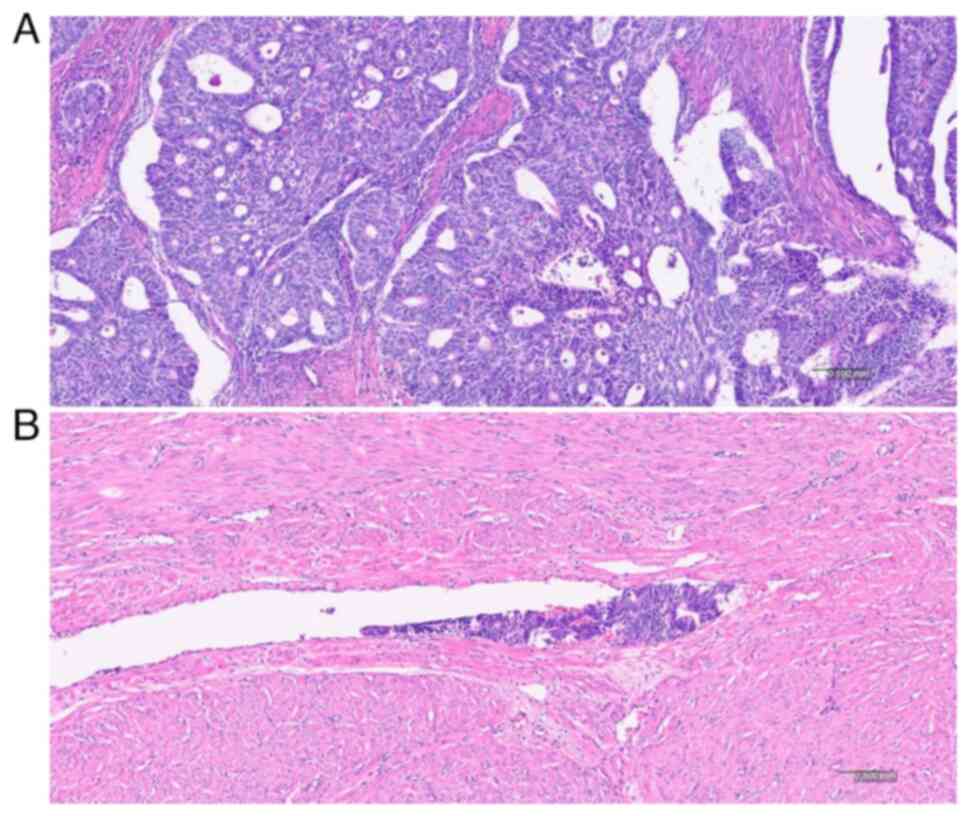

Laboratory findings including fasting blood sugar, HbA1c, C-reactive protein and CA125 levels, were unremarkable. First, the patient underwent open reduction and internal fixation involving screw fixation for a right ankle syndesmosis injury, distal fibular fracture, and ankle posterior malleolar fracture. The postoperative follow-up showed successful healing and functional recovery (Fig. 1). A total of 4 weeks later, robot-assisted total hysterectomy, bilateral salpingectomy and sentinel lymph node sampling were performed. Final pathology revealed stage 1B, grade 2 endometroid adenocarcinoma with substantial lymphovascular space invasion (LVSI) (Fig. 2). Regional lymph node involvement was not identified. The peritoneal fluid cytology was negative for malignant cells. Immunohistochemistry staining revealed p53 (-), MLH1 (+), PMS2 (+), MSH-2 (+) and MSH-6 (+). The patient received 50.4 Gy external beam radiotherapy (EBRT) to the whole pelvis. Chest and abdominopelvic imaging (CT or MRI) were checked every 6 months. The 26-month postoperative follow-up showed that the patient was disease-free. The present study was reviewed and approved by the Institutional Review Board of Pusan National University Hospital (approval no. 2404-017-138; Busan, Korea). Written informed consent was obtained from the patient for publication of data of her medical case and associated images.

Figure 2

Microscopic findings. (A) The tumor exhibited endometrioid differentiation with focally solid non-squamous growth pattern (H&E stain, x100 magnification). (B) Lymphovascular invasion was present (H&E stain, x100 magnification).